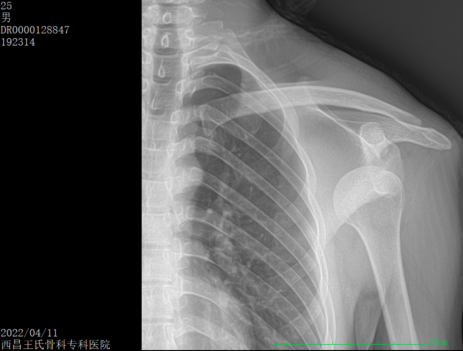

手法复位病例一:肩关节脱位

image.png image.png

复位前                                复位后